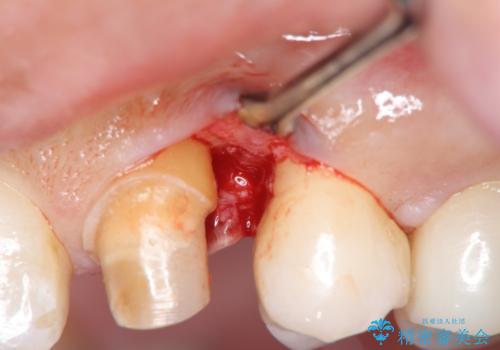

その後、手術をしてしっかり骨の位置を修正し、歯を引っ張り出した時に増殖した余分な歯ぐきを薄くする歯周外科治療も行なっています。

術後は計画通り歯ぐきの腫れが収まり、炎症に強い歯ぐきになりました。

左:虫歯を除去したところ。遠心が歯ぐきより深い状態です。中:そのままかぶせようとすると、遠心が歯ぐきが腫れやすい状態です。右:エクストリュージョンをしたことで、遠心の歯ぐきの腫れが収まっていることがわかります。